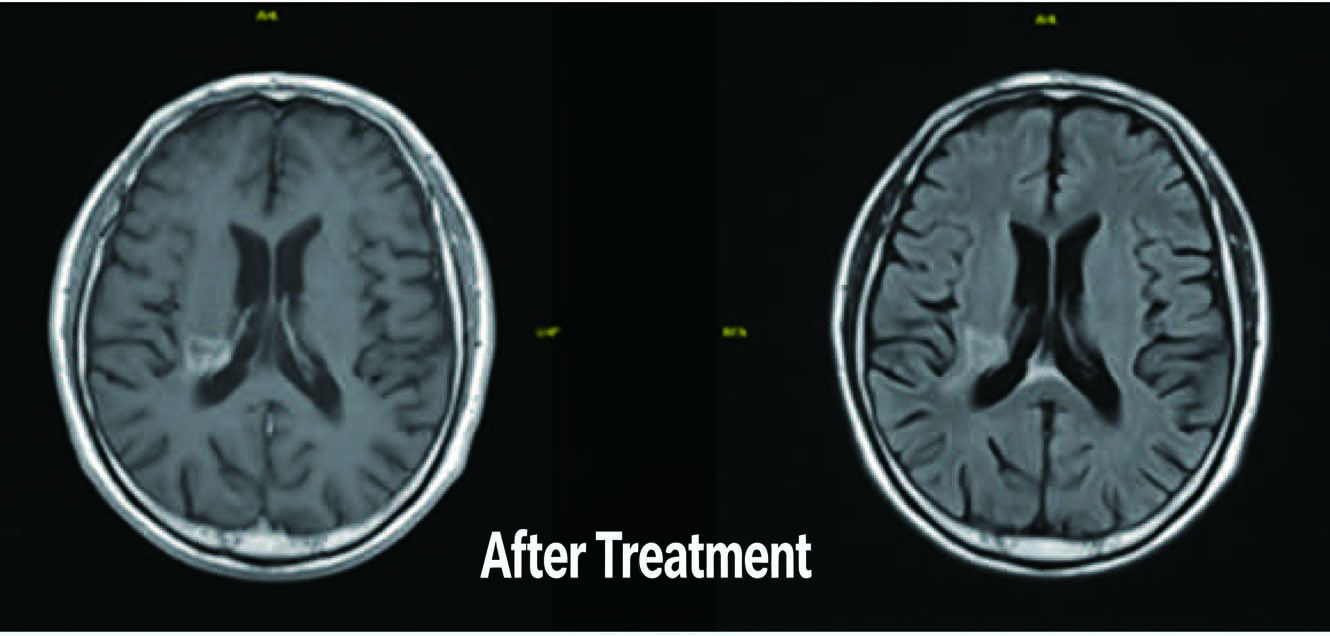

After Treatment

Patient: Male, 66 years old

Diagnosis: Nasopharyngeal malignant tumor (Undifferentiated non-keratinizing carcinoma of nasopharynx) Treatment Period: April 12, 2021, to May 27, 2021

Treatment Modality: VMAT Radiotherapy (Prescribed dose to Planning Gross Tumor Volume: 69.96 Gy in 33 fractions, 2.12 Gy per fraction)

Outcome: After-treatment continuous follow-up examinations revealed gradual shrinkage of the nasopharyngeal mass.MRI results on January 5, 2023, showed complete disappearance of the nasopharyngeal mass, with significant reduction in previously positive lymph nodes.